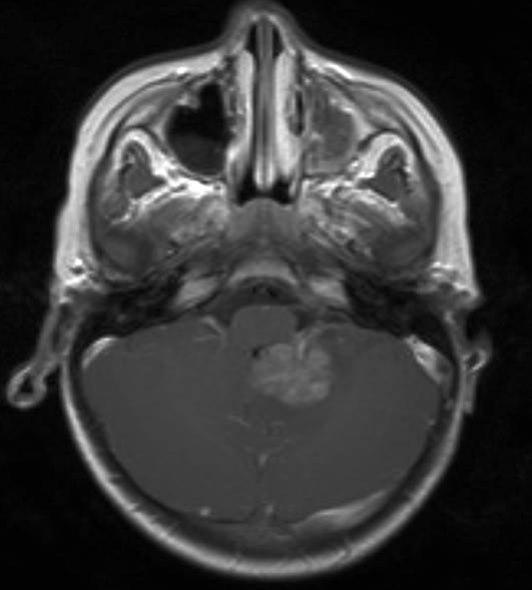

Atypisk teratoid rhabdoid tumor, aksialt snitt

Gjengitt med tillatelse av Radiologisk avdeling, Universitetssykehuset Nord-Norge